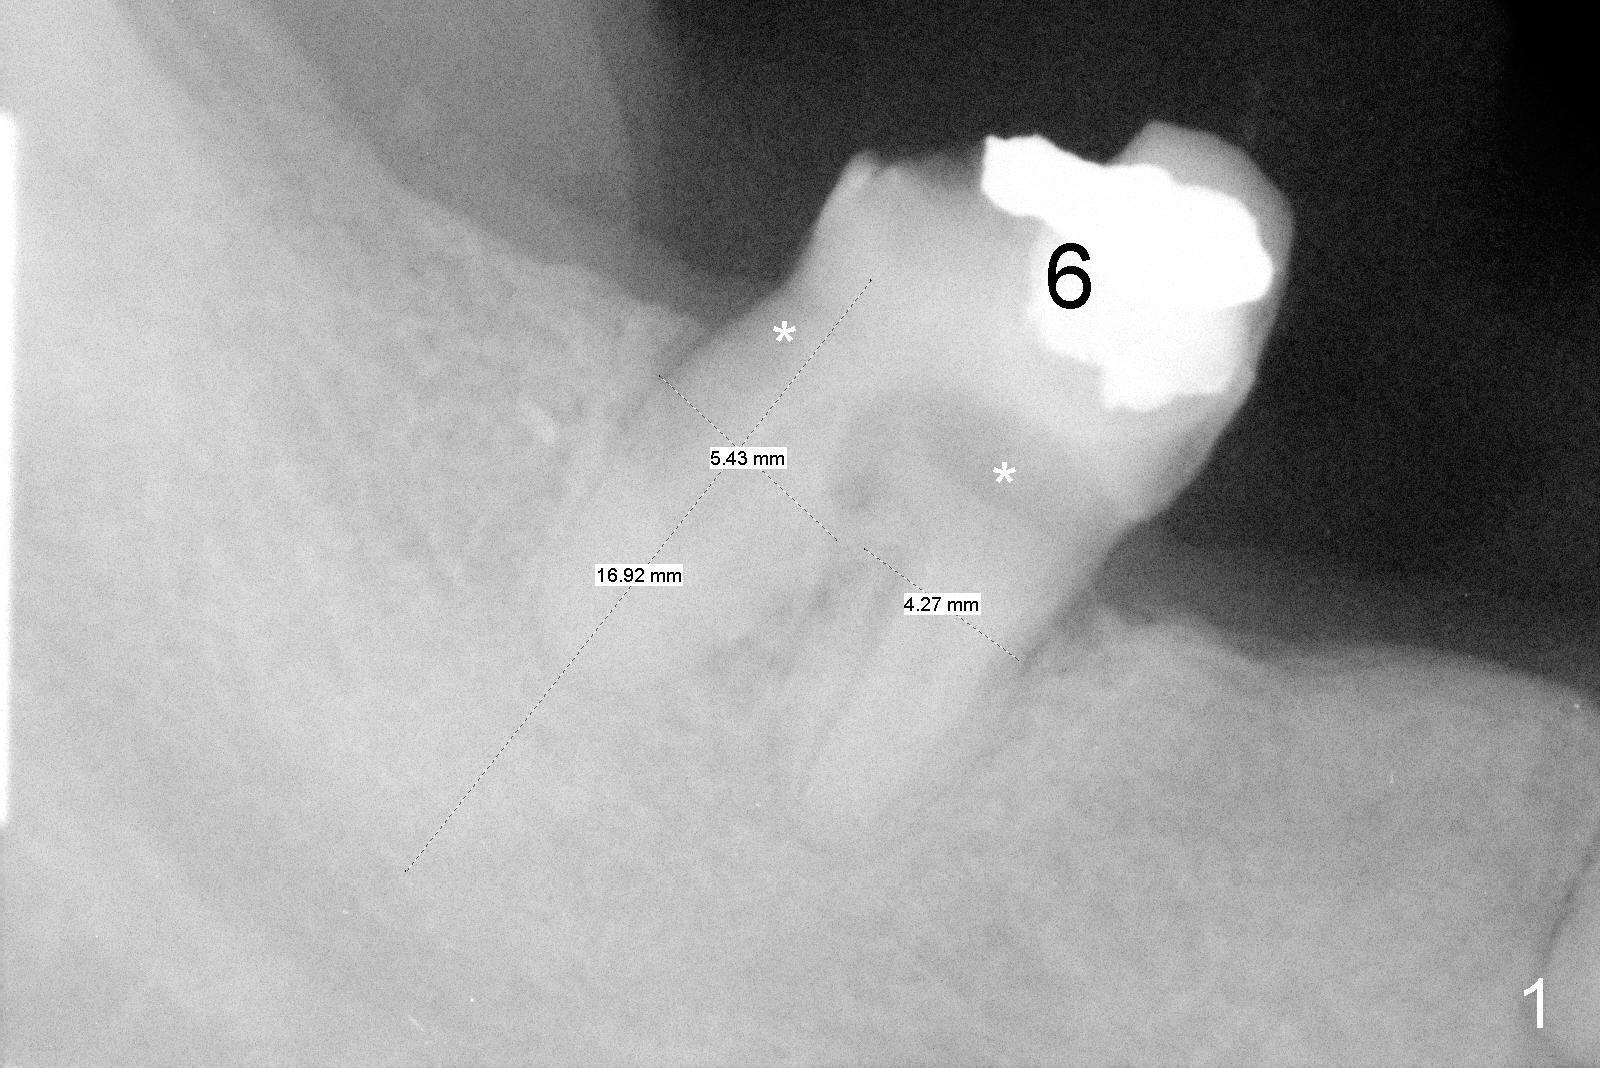

The lower right bridge (from canine (Fig.2: 3) to 1st molar (Fig.1: 6)) fails while a 77-year-old man is undergoing chemotherapy for urinary bladder cancer.  The abutments of the bridge are extracted without plan for implants (Fig.4).   Four months later, the patient returns for implants (Fig.3), but the ridge is narrow (Fig.5).  While 2 of 3x14 mm 1-piece implant are placed at the canine and 1st bicuspid sites, 2 piece ones at the 2nd bicuspid and 1st molar sites (Fig.6: 3.5x11 mm, 5x14 mm).  Soft (Fig.7-10) and hard (Fig.11) tissues heal 1 week (Fig.7) and 4 months (Fig.8-11).  There is minimal bone resorption 1 year 7 months post cementation (Fig.12,13, non-splinting).  It appears that narrow diameter implants are a valid solution to narrow ridge at the sites of the lower canine and premolar.  As long as there are enough implants for function, the crowns are not necessary to be splinted.  Surprisingly, the patient starts flossing after implant restoration.  Retrospectively an immediate provisional bridge should have been fabricated.